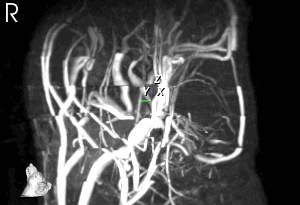

The PET Technology

FDG distribution

PET images living systems by recording high-energy γ-rays emitted from within the subject. The source of the radiation comes from positron-emitting-bound biological molecules, such as 18F-FDG (fludeoxyglucose), which is injected into the test subject. As the radioisotopes decay, they emit positrons which annihilates with electrons found naturally in the body. This produces 2 γ-rays at ~180° apart, which are picked up by sensors on opposite ends of the PET machine. This allows individual emission events to be localized within the body, and the data set is reconstructed to produce images.

The MRS-7000 system allows simultaneous PET/MR imaging, and can image whole body mouse and rat heads.